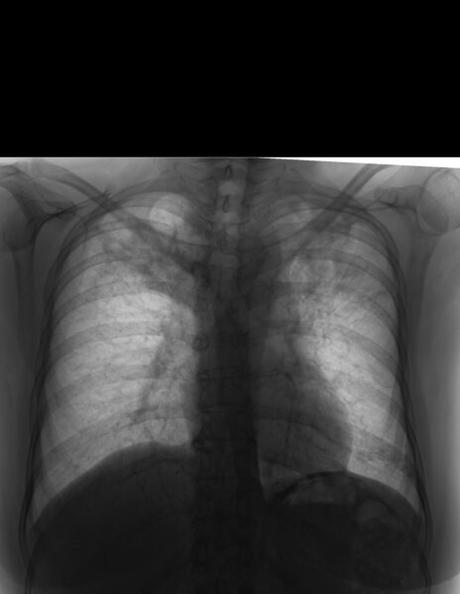

PA DE TORAX (TELE DE TORAX)

LA PROYECCION RADIOLOGICA OBTENIDA NOS MUESTRA LOS SIGUIENTES HALLAZGOS:

-Tejidos blandos, con densidad conservada, simétricos, sin evidencia de alteraciones.

-Estructuras óseas, sin evidencia de lesiones líticas, blásticas o perdida de la contigüidad. Se observa convexidad derecha de columna dorsal. Existen osteofitos marginales.

-Vía aérea permeable, tráquea con leve desplazamiento hacia la derecha por botón aórtico.

-Mediastino, con ensanchamiento de su porción superior por arco aórtico y aorta descendente.

-Corazón, con índice cardiotorácico menor a 0.5.

-Hilios pulmonares, y pulmonar izquierdo oculto.

-Trama bronco-vascular, conservada.

-Campos pulmonares, con patrón retículo nodular difuso, así como presencia de áreas en vidrio esmerilado en lóbulos superiores de ambos pulmones, con bronquiectasia en pulmón derecho.

-Recesos cardiofrénicos y costofrénicos libres.

OPINIÓN RADIOLÓGICA:

EN EL PRESENTE ESTUDIO RADIOGRÁFICO, CON DATOS DE NEUMOPATÍA CRÓNICA INTERSTICIAL (ENFERMEDAD GRANULOMATOSA), BRONQUIECTASIA EN LÓBULO PULMONAR DERECHO Y ÁREAS DE CONSOLIDACIÓN EN AMBOS LÓBULOS SUPERIORES.

CORRELACIONAR CON DATOS E HISTORIA CLINICA DEL PACIENTE